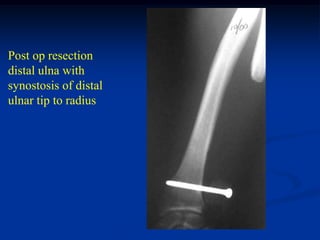

Case #253

29 year male

recent fracture ulna

18 months later

with desmoid tumor

at fracture site

Post op resection

distal ulna with

synostosis of distal

ulnar tip to radius